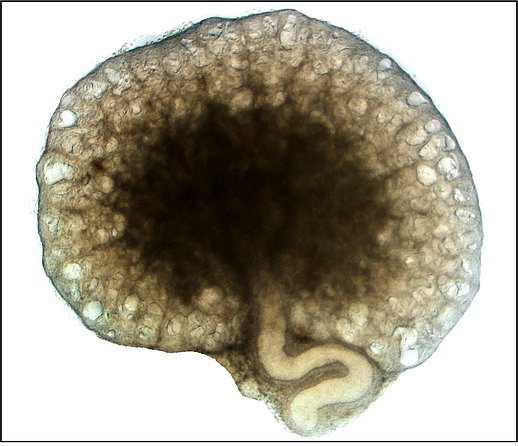

In our group we are mainly interested in the mechanisms of cyst growth in polycystic kidneys. There is a variety of polycystic kidney diseases that are often hereditary. The most frequent form is the autosomal dominant polycystic kidney disease ADPKD. It affects one in one thousand people and leads to the development of various fluid-filled cavities (cysts) in both kidneys. Cysts then grow continuously over time which causes compression of adjacent unaffected tissue which often results in loss of renal function. Cyst expansion can mainly be attributed to secretion of chloride and fluid by the cyst epithelium into the interior of the cyst. We investigate proteins but also environmental factors that may play a role in cyst secretion. Our long-term objective is to find strategies in order to inhibit cyst growth and therefore preserve renal function.

Continuous cyst growth results in progressive hypoxia in polycystic kidneys which in particular leads to expression of the hypoxia-inducible factor HIF-1α in cyst-lining cells. We analyse the effects of HIF-1α on cyst expansion.

Chloride secretion into the cyst lumen is mediated by apically expressed chloride channels. Next to the cAMP-dependent CFTR chloride channel also Ca2+-activated chloride channels are involved. Therefore, we investigate the impact of anoctamins, a new family of Ca2+-activated chloride channels, on cyst secretion.

Activation of Ca2+-activated chloride channels often follows stimulation of purinergic receptors (P2Y- and P2X receptors) by extracellular ATP. We study the relevance of purinergic receptors for secretion-dependent cyst growth.